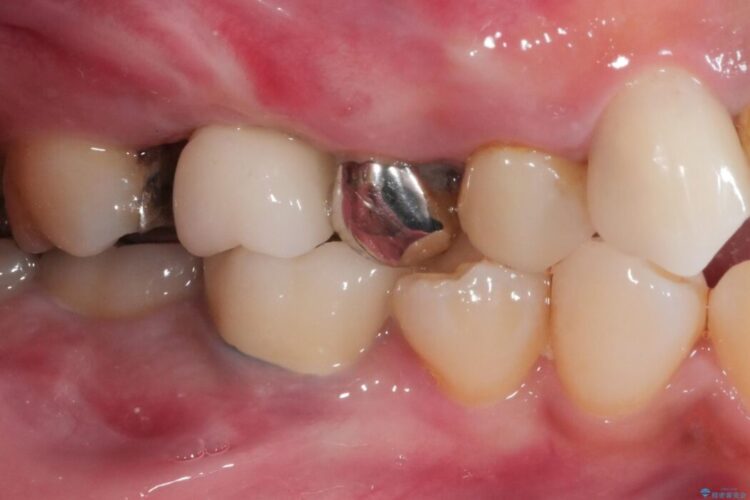

【40代男性】銀歯をセラミックにやり替え

【40代男性】銀歯をセラミックにやり替え ビフォー 【40代男性】銀歯をセラミックにやり替え アフター

銀歯をセラミックにやり替えたいとご来院された患者様です。